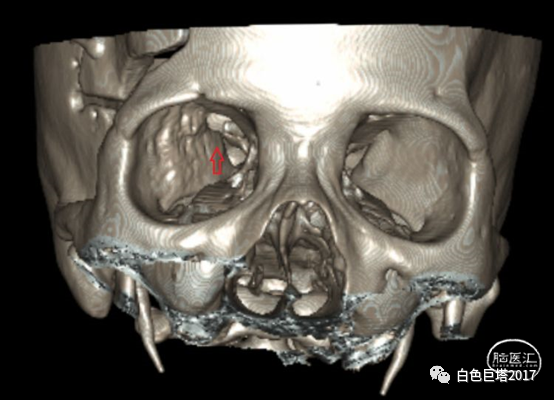

下图红箭头示磁共振增强提示局部脑膜强化

外院曾行磁共振+增强检查提示右侧蝶骨大翼异常信号,考虑骨纤维异常增殖,未考虑肿瘤。

两种疾病临床表现相似,容易误诊。主要的鉴别点就是增强CT或MRI是否存在眶、颅内软组织肿块。